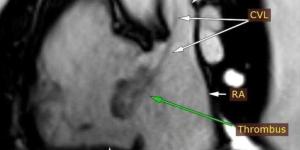

وحدة تصوير القلب بالرنين المغناطيسي بمستشفي سوهاج الجامعي الجديد تُشخّص حالة نادرة لمريض وتُسهم في علاجها الفوري - بلس 48